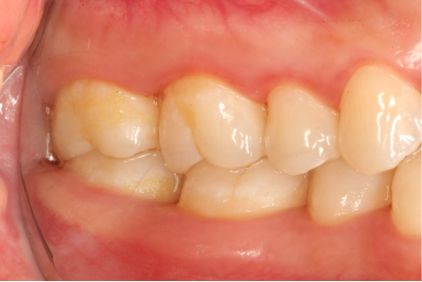

超声洁刮治术后5周

采用PT5牙周治疗仪进行全口超声龈上洁治术、超声龈下刮治术。术后5周复查可见牙龈炎症明显减轻,仍有轻度炎症,复查发现患者口腔卫生维护欠佳,再次进行口腔卫生宣教。